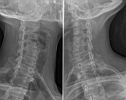

Thorax – Abdomen – Schedel – CWZ – DWZ – LWZ – Bekken – Full Spine – Schouder – Bovenarm – Elleboog – Onderarm – Pols – Hand – Heup – Bovenbeen – Knie – Onderbeen – Enkel – Voet – Full Leg – Transit – Colonografie – E.R.C.P. – I.V.P. – Cystografie – Hysterografie